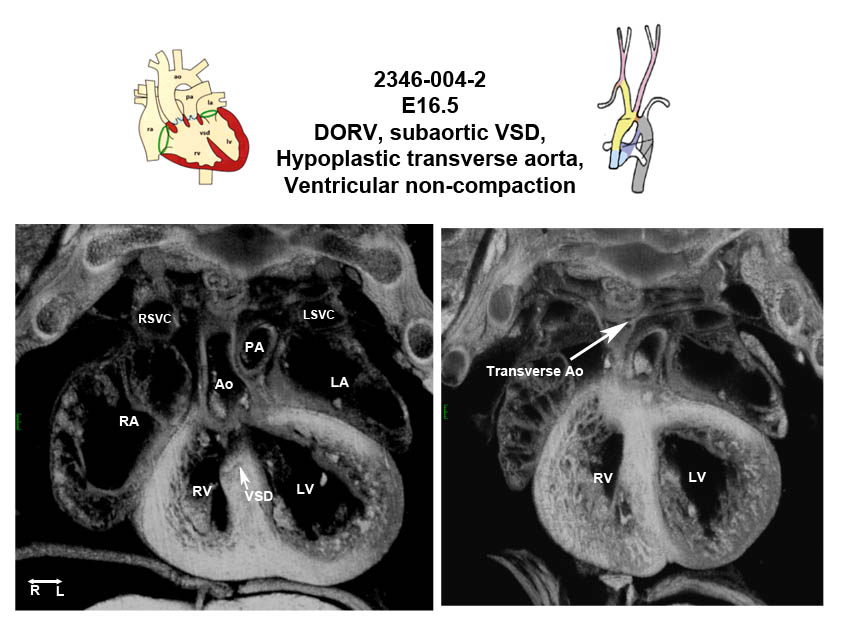

Caption EFIC Summary

Mapk7b2b2346Clo mitogen-activated protein kinase 7; Bench to Bassinet Program (B2B/CVDC), mutation 2346 Cecilia Lo

Mapk7b2b2346Clo/Mapk7b2b2346Clo C57BL/6J-Mapk7b2b2346Clo